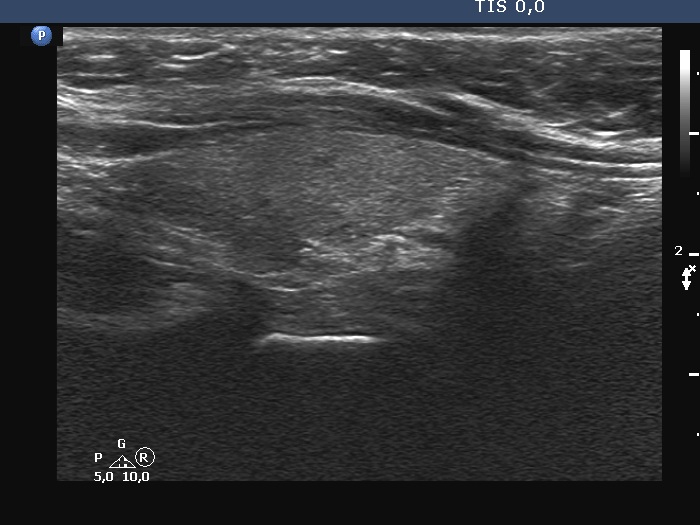

Introduction - case 816 (ultrasonographic picture 8)

Left lobe, longitudinal scan.